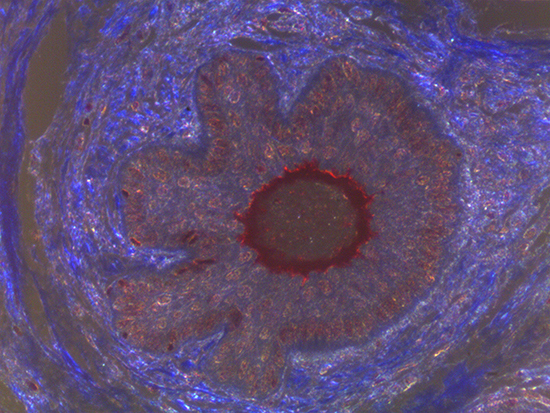

Figure 2: Darkfield Imaging of Dermal Tissue

When comparing Figures 1 and 2, the visual differences are significant. A brightfield image is formed with the illumination source below the sample, and then transmitted light propagates through the sample to the sensor forming a bright, white background with sharp color. A darkfield image is formed by directing light at an oblique angle through the sample, forming a hollow cone of light which is collected by the objective. Darkfield illumination typically yields a dark background with sharp color, but in the case of Figure 2, the collagen and muscle fibers interfered with the light path and caused a blur of light and color. The dark background is hardly evident and only two distinct colors are visible. When analyzing histological stains, brightfield illumination is the preferred technique for lighting a sample.

When comparing Figure 3 with Figure 4, there is once again a significant visual difference. The most obvious feature is the change in color from green to red due to a different hardcoated filter being positioned in the optical path. The less obvious difference is the varying contrast levels caused by the filters at specific regions of the dermal tissue. For example, Figure 3 exhibits a distinct ring at the central region of the cell with additional matter within. In Figure 4, the ring is extremely faint and the internal matter is not visible. With that said, the cell and surrounding dense materials are more evident in Figure 3, whereas the muscle fibers and collagen are more pronounced in Figure 4.